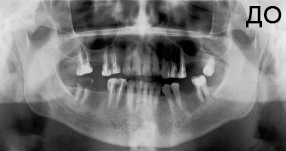

4 работы в портфолио

Удаления зубов любой сложности. Пародонтология (закрытый, открытый кюретаж, лоскутные операции, рецекция верхушки корня, вестибулопластика, френулотомия, френулоэктомия). Переостотомия, вскрытие абсцессов и других воспалительных процессов. Цистотомия, цистэктомия. Имплантология (установка имплантатов различных систем с осложненными анатомическими условиями, направленная костная регенерация, открытый синус-лифтинг, закрытый синус-лифтинг, пластика альвеолярного гребня).

Акопян Антон Владимирович: портфолио (4)